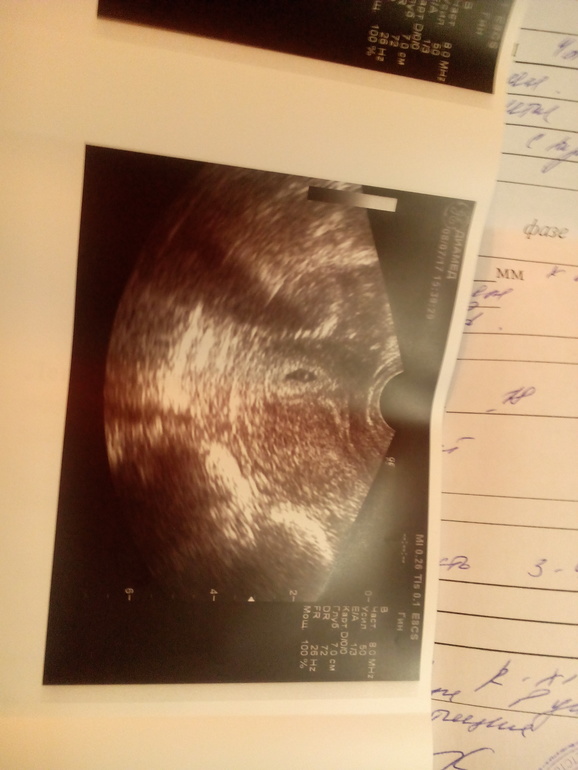

А узи что показало? Вообще, трудно поверить, что врач сослалась на нормы хгч на таком сроке...тут только узи имеет смысл

Елена

УЗИ она мне вчера сказала, что по размеру пя оно соответствует 3-4 АКУШЕРСКИМ неделям!!! Она это подчеркнула, что не эмбриональным, а акушерским

В 3 акушерских недели, ПЯ не видно вообще ( ибо это аж за неделю до М)

В общем, в данной ситуации только смотреть узи в динамике. Рост хгч на этом уровне вообще не показателен. Старайтесь сохранять спокойствие, можно персен или любое другое растительное успокоительное, и узи через неделю